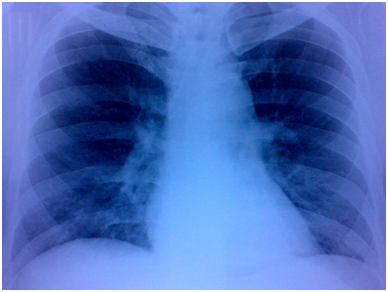

A 36years old male presented to our institute with history of atypical chest pain and breathlessness on exertion class II for past 2years. He had past history of pericardial effusion 3years back for which he took full course of ATT. General physical examination was unremarkable, although cardiovascular examination revealed loud P2 component of second heart sound and grade III/VI ejection systolic murmur over the pulmonary area. Electrocardiogram revealed RAD of QRS complex, incomplete RBBB & RVH. X-ray chest PA view had prominent right ventricular outflow tract with no evidence of hilar or paratracheal lymphadenopathy (Figure 1).

Figure 1 X-ray chest PA view had prominent right ventricular outflow tract with no evidence of hilar or paratracheal lymphadenopathy.